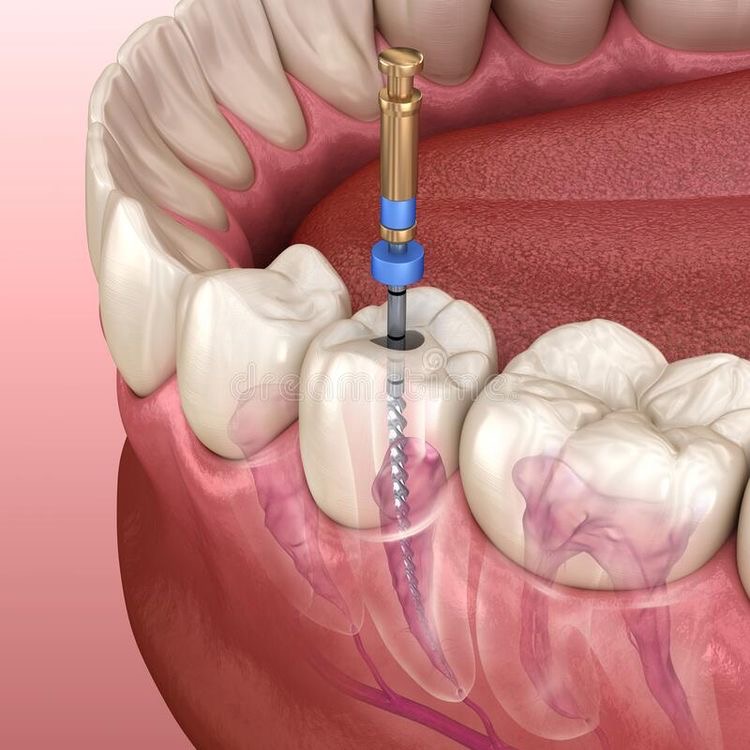

Endodontic Therapy

Endodontic therapy consists of a series of treatments, including removing pulpal tissue, filing and shaping root canals, obturation of the root canal space, and placement of a permanent restoration for the tooth.